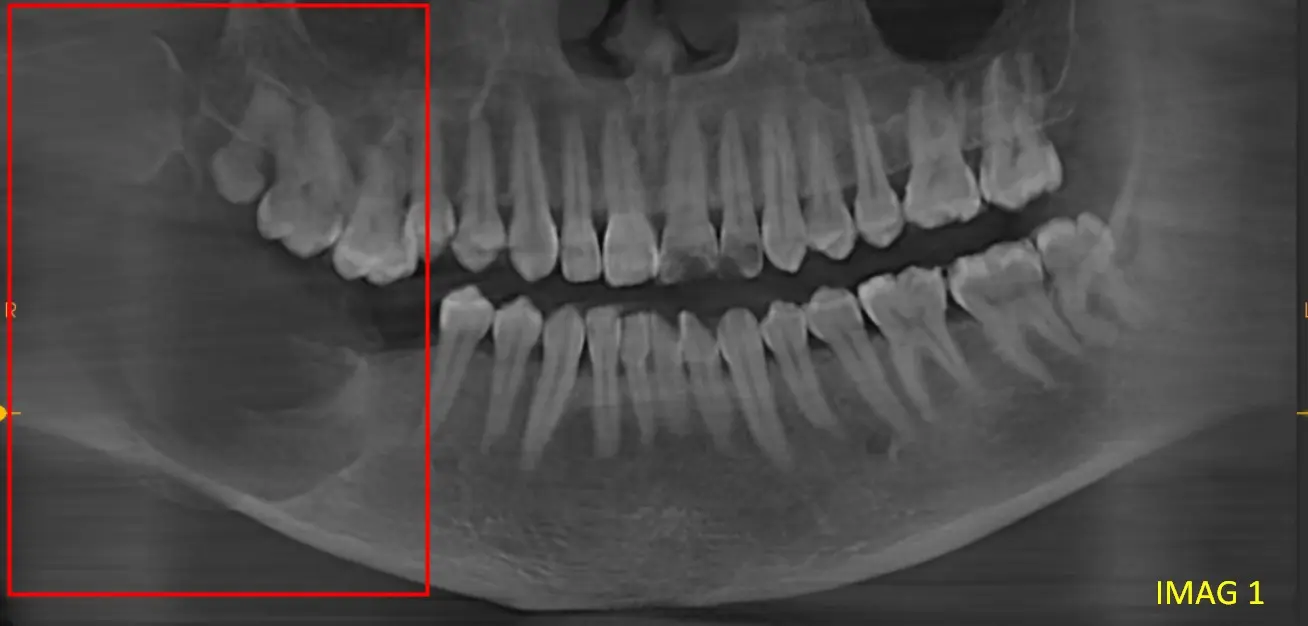

Se observa imagen hipodensa unilocular, bien delimitada que ocupa el área del ángulo mandibular extendiéndose hacia la rama ascendente (ver imagen 1).